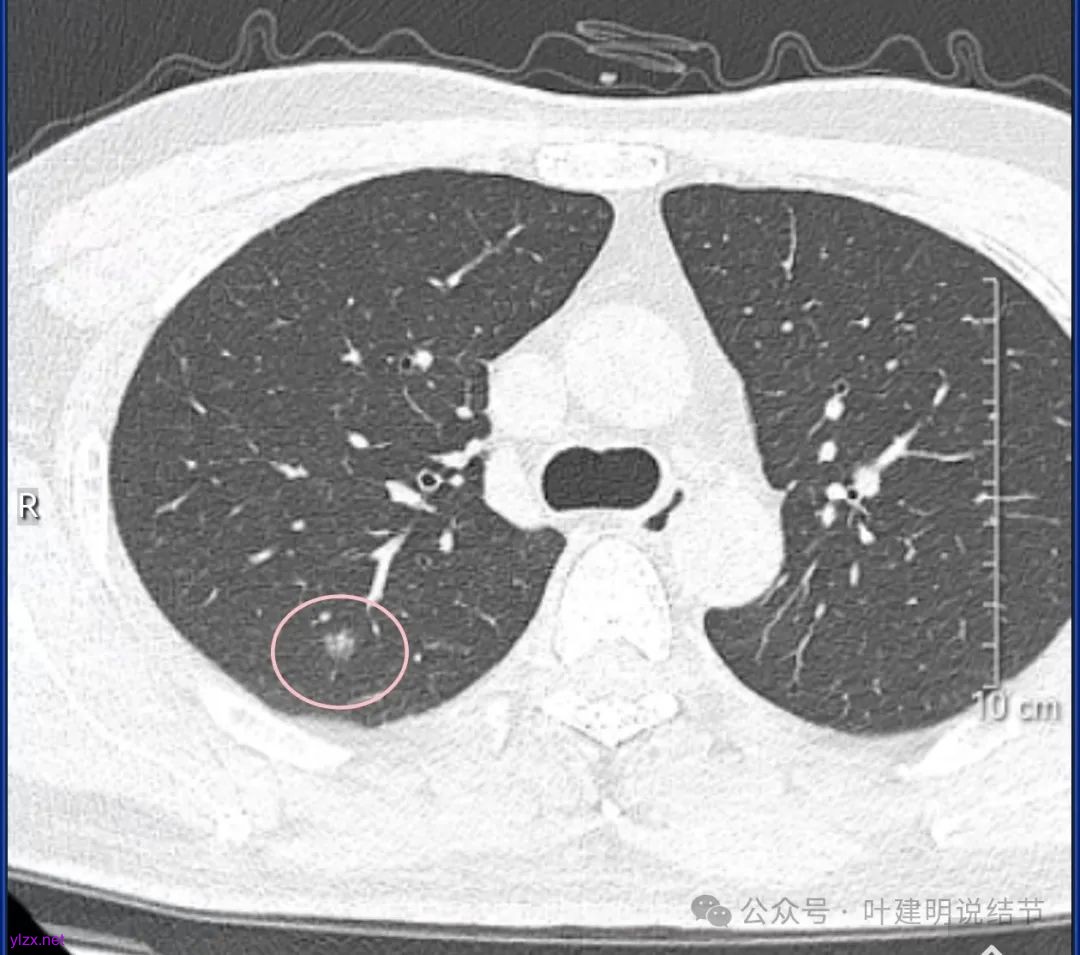

结友男性,41岁,具体病史记不得了,下面是请他重新发我的术前CT报告中截图的影像。

主病灶位于右上叶后段(与尖段交界附近,也可能是尖段的,需要三维重建明确),磨玻璃密度,灶内点状偏高密度,整体轮廓与边界清楚。

下叶背段有一实性结节,但没有找到其他磨玻璃结节。可以反馈的术后病理说下叶楔形切除了有个结节是肺泡上皮增生。大概不会是这处实性的,可能是很淡的,不容易找到的一处结节。算了,不管它。也不知道这处实性的有没有处理,还是不需要处理。